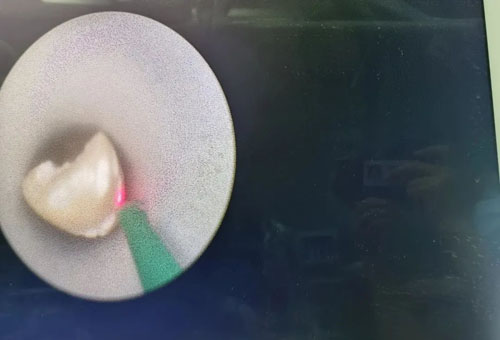

經(jīng)皮腎鏡鈥激光碎石取石中

在程廣舟副院長(zhǎng)的指導(dǎo)下,程波副主任為患者實(shí)施手術(shù)。患者結(jié)石質(zhì)地堅(jiān)硬,碎石困難,在麻醉醫(yī)師與手術(shù)室護(hù)士的通力配合下,該患者順利完成雙側(cè)“無(wú)管化”經(jīng)皮腎鏡碎石取石術(shù)。從精準(zhǔn)穿刺到擴(kuò)張,再到手術(shù)結(jié)束,僅僅用了1個(gè)半小時(shí)。手術(shù)過(guò)程中,麻醉醫(yī)生密切觀察患者情況,術(shù)后患者順利復(fù)蘇,術(shù)后恢復(fù)良好,未出現(xiàn)發(fā)熱情況,術(shù)后復(fù)查腹部平片未見(jiàn)結(jié)石殘留,患者及家屬非常滿意。